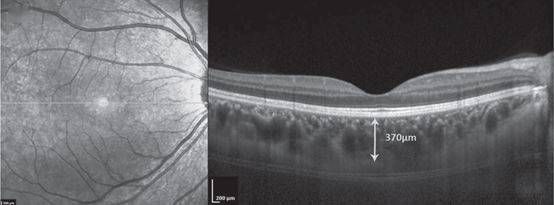

局限性脉络膜凹陷合并中心性浆液性脉络膜视网膜病变一例

中心凹下脉络膜厚度测量具体测量及正常值可以参照下图.